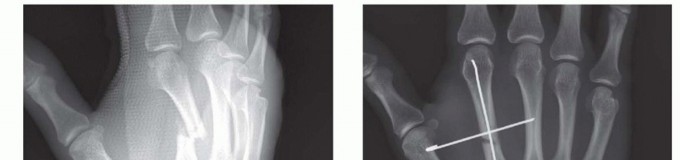

RETROGRADE COLLATERAL RECESS PINNING

TECH FIG 1 • A. Retrograde (collateral recess) pinning. B,C. Angled distal metacarpal fracture. (continued)

TECH FIG 1 • (continued) D,E. Fracture stabilized with two pins that have been advanced to the base of the metacarpal. (Copyright Thomas R. Hunt III, MD, DSc.)